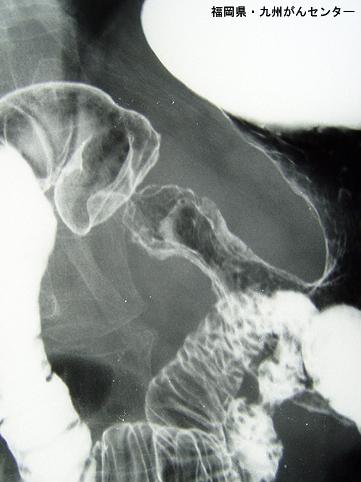

질환(병리주체)의 분류 악성 상피성종양/선암

부위(장기별) 위(부위)/2개 이상

검사방법 X-P

종양의 육안분류 4형(미만침윤형)/

종양의 최대경(밀리미터) 40이상

종양의 심달도 ss(a1)